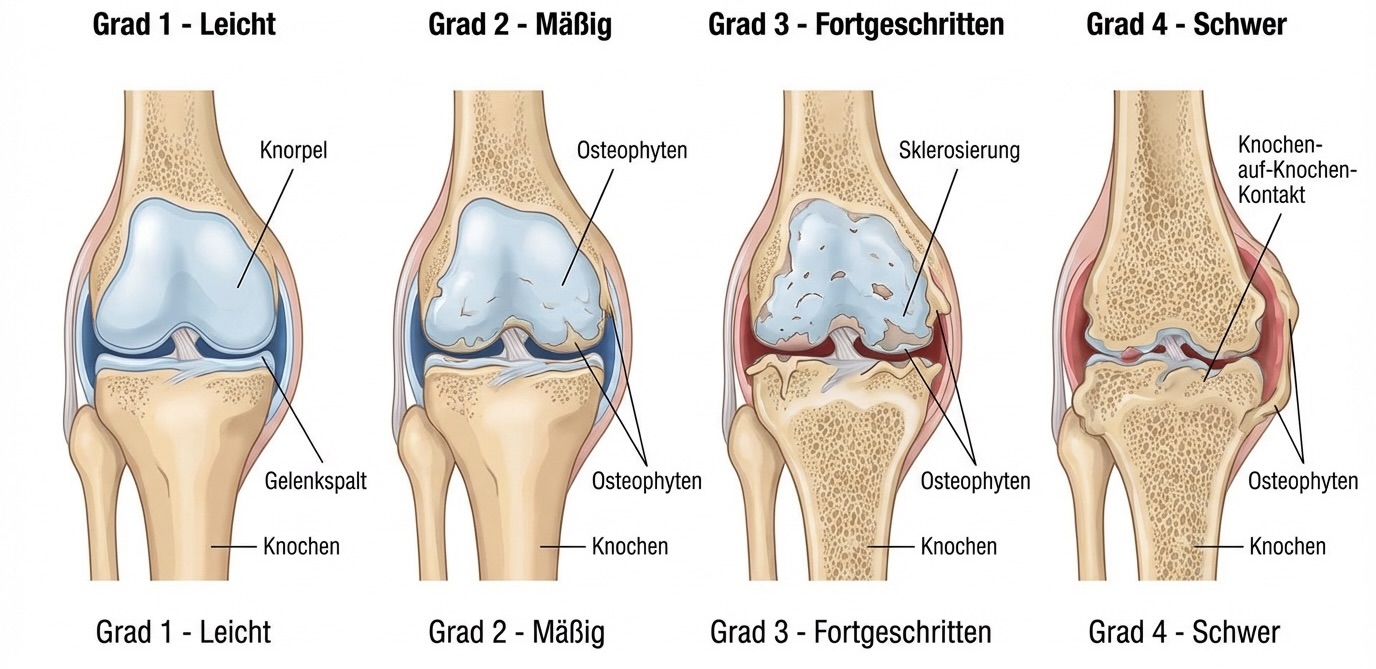

- Fortgeschrittene Kniearthrose (Gonarthrose)

Wann ist eine Knieprothese notwendig?

Eine Knie-TEP wird empfohlen, wenn konservative Behandlungen (Medikamente, Physiotherapie, Injektionen, Orthesen) nicht mehr ausreichend helfen und Sie unter anhaltenden Schmerzen sowie deutlichen Bewegungseinschränkungen im Alltag leiden. Typische Indikationen sind fortgeschrittene Arthrose (Gonarthrose), rheumatoide Arthritis, posttraumatische Arthrose oder Knochennekrose.